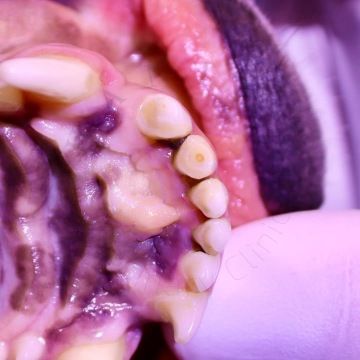

Trauma zubů je u společenských zvířat bohužel běžná a je často důsledkem nevhodných žvýkacích hraček nebo agresivního chování při žvýkání a hraní. V mnoha případech má zlomený zub obnaženou dřeň. Pokud je trauma čerstvé (trvá méně než 48 hodin), lze zvolit terapii vitální amputace pulpy, aby zub zůstal živý. To je zvláště důležité u mladých zvířat, která mohou mít zuby s nedokončeným vývojem kořene (hrot kořene ještě není uzavřen). V případě téměř expozice dřeň není aktivně vystavena vnějšímu prostředí. Na dřeni je sice stále velmi tenká vrstva dentinu, ale zde existuje vysoké riziko nevratné pulpitidy (pro zvíře bolestivý stav). Třetí možností využití terapie vitální amputace pulpy je v případech liguovezních mandibulárních špičáku (spodné špičáky jsou vyhnuté směrem dovnitř k jazyku) jako ortodontická procedura. Takhle rotované spodní špičáky následně zraňují tvrdé patro zvířete a můžou následně způsobit oronazální píštěl. Oronazální píštěl je abnormální komunikace mezi dutinou ústní a nosní, která vede k chronickým infekcím horních cest dýchacích. Provedením redukce korunky a terapie vitální amputace pulpy na dolních špičácích je dosaženo bezbolestné okluze bez ztráty těchto funkčně důležitých zubů.